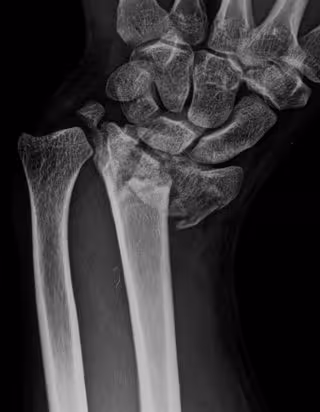

Archivo - Fractura de radio

Archivo - Fractura de radio - HOSPITAL LA LUZ - Archivo

Son algunos de los datos que se han puesto de relieve en el Encuentro con el experto 'Fracturas Vertebrales Osteoporóticas: ¿Cuáles tratamos?', celebrado en el marco del 44 Congreso Nacional de Medicina Interna de la SEMI, en el que se ha reiterado que "las fracturas vertebrales son el tipo de fractura más común seguida de la de cadera, muñeca y otras como la del antebrazo, húmero, tibia y peroné".